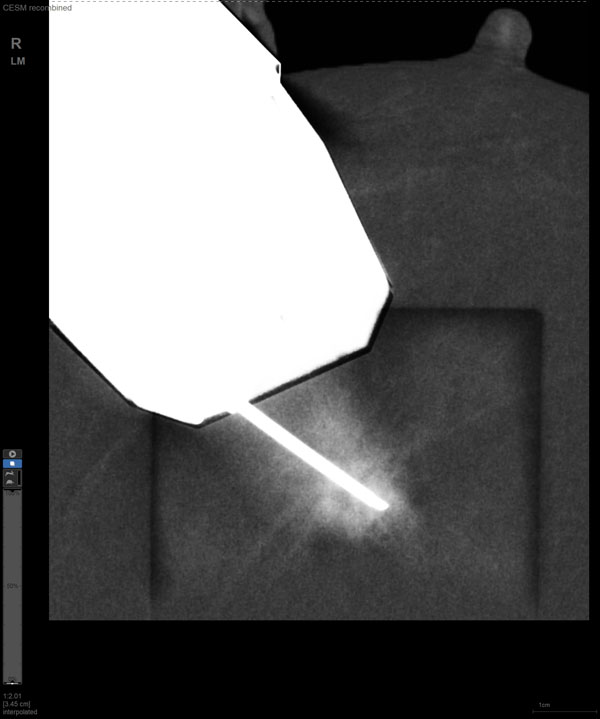

近日,我院放射科成功开展首例“乳腺对比增强X线摄影(contrast-enhanced mammography, CEM)引导下穿刺活检术”。该技术定位精准、安全微创、简便快捷、舒适经济,通过对穿刺获得的肿物组织标本进行病理检查,为临床后续治疗提供科学依据,为乳腺癌患者早诊早治带来新的福音。

CEM引导下穿刺

某患者增强磁共振成像MRI显示肿瘤周边有活性,中心区域有组织坏死。为得到准确的病理结果,穿刺靶区需避开肿物坏死区域。在与患者主管医生充分讨论后,放射科医生为患者行CEM引导下穿刺活检术。术中,CEM检查肿物同样显示为环形强化,巧妙避开坏死区域后,穿刺靶区选择了肿物增强早期明显强化区域,术程顺利,仅用时15分钟。术后该患者病理结果为浸润性导管癌Ⅱ级。